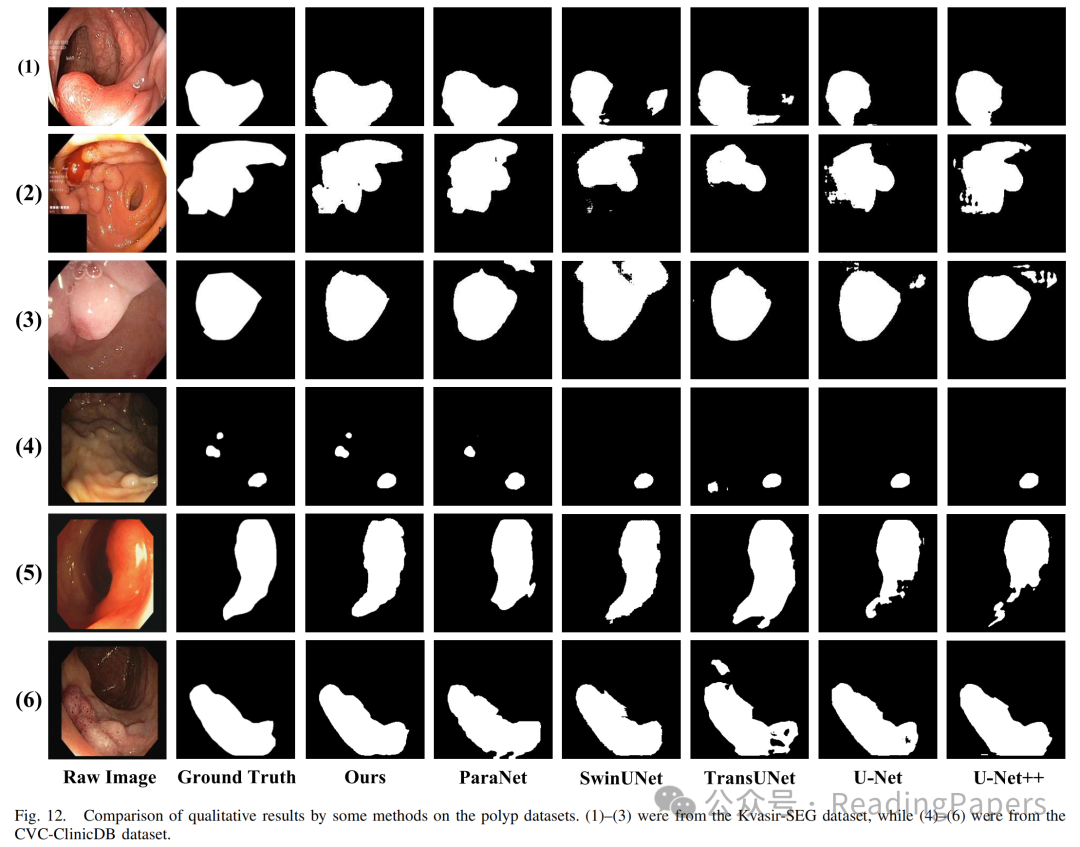

Transformer通过自注意力机制在医学图像处理中取得了显著进展,能够建模长距离语义依赖关系,但其缺乏卷积神经网络(CNN)捕捉局部空间细节的能力。本文提出了一种基于混合CNN-Transformer(MixFormer)特征提取骨干网络的新型分割网络,旨在提升医学图像分割的效果。MixFormer网络在下采样过程中无缝集成了Transformer和CNN架构的全局和局部信息。为了全面捕捉跨尺度的视角,作者引入了多尺度空间感知融合(MSAF)模块,有效实现了粗粒度与细粒度特征表示之间的交互。此外,作者还提出了混合多分支扩张注意力(MMDA)模块,用于在编码和解码阶段之间弥合语义差距,同时强调特定区域。最后,作者采用基于CNN的上采样方法来恢复低级特征,显著提高了分割精度。通过在多个主流医学图像数据集上的实验验证,MixFormer表现出卓越的性能。在Synapse数据集上,该方法达到了82.64%的平均Dice相似系数(DSC)和12.67 mm的平均Hausdorff距离(HD)。在自动心脏诊断挑战(ACDC)数据集上,DSC达到了91.01%。在国际皮肤成像协作(ISIC)2018数据集上,模型的平均交并比(mIoU)为0.841,准确率为0.958,精确率为0.910,召回率为0.934,F1得分为0.913。在Kvasir-SEG数据集上,平均Dice为0.9247,mIoU为0.8615,精确率为0.9181,召回率为0.9463。在CVC-ClinicDB数据集上,平均Dice为0.9441,mIoU为0.8922,精确率为0.9437,召回率为0.9458。这些结果表明,MixFormer在分割性能上优于大多数主流分割网络,如CNN和其他基于Transformer的结构。